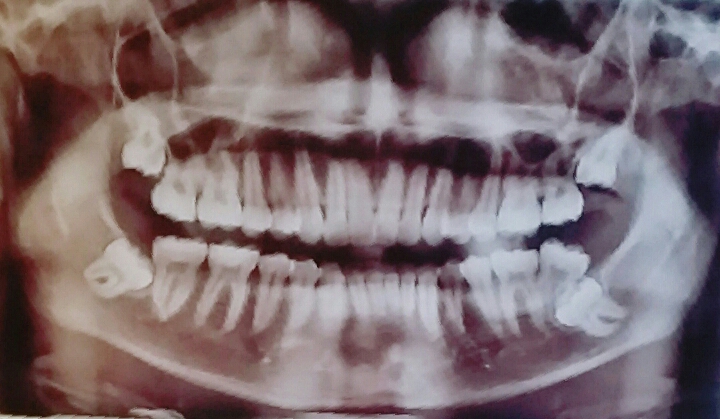

ทันตกรรม

ทันตกรรมจัดฟัน

ผ่าฟันคุดมีโอกาสปากชาไม่หายไหม